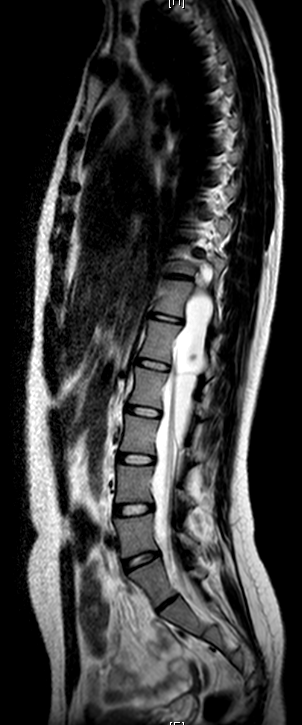

主诉:双下肢乏力4年,加重半年。 病史:患者于4年前无明显诱因出现双下肢乏力,双手支撑地面才能下蹲,无行走困难,无腰部酸痛,无双下肢疼痛、麻木感,大小二便未见异常。半年前,患者诉双下肢乏力及蹲下困难加重,难以下蹲及上下楼梯,无双下肢疼痛、麻木感,大小二便未见异常。遂至外院行MR检查提示:T11-L3水平椎管内蛛网膜囊肿,并相应脊髓圆锥、马尾神经受压移位、聚集。患者一般情况尚可。

查体:双侧踝关节呈跖屈位。腰3/4棘突有轻压痛。右踇背伸肌3-级,左踇背伸肌4级,右踝背屈肌3级,左踝背屈肌4级,右股四头肌2级,左股四头肌3级。右侧膝反射未引出(-),左侧膝反射(+),右侧踝反射(+),左侧踝反射(++),双侧踝阵挛、Babinski征(-)。双侧股神经牵拉(反Lasegue)(+),左侧4字征(+)。

诊断:胸腰椎管内占位待查 治疗:入院后尽快完善相关检查,初步明确胸腰椎管内占位原因,初步评估患者病情及是否可进行手术。经治疗组讨论后,拟后路蛛网膜囊肿切除+栓系松解+钉棒内固定术”,术后根据病理决定是否进行下一步治疗。